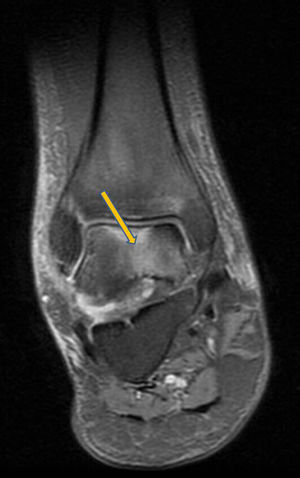

Clinical CaseA 41 year old male with no medical history of interest, presented at the surgery with right knee pain and minimum trauma. Diffuse bone marrow oedema involving the external condyle was reported. Four months later he presented with bone marrow oedema in the ipsilateral internal condyle (Fig. 1). In other magnetic resonance images we found new bone marrow oedema extension, in the internal femoral condyle of the contraleteral knee and later in the external condyle and pain in the right knee, the NMI of which also showed bone marrow oedema (Figs. 2 and 3). Treatment with NSAIDS was administered and partial load-bearing but this was ineffective.

In the differential diagnosis its distinction is interesting, compared with the algodystrophy of Südeck, reflex sympathetic dystrophy or complex regional pain syndrome. This condition is painful after a traumatic event, sometimes with low intensity, and presents with allodynia (or intense pain on response to non painful stimuli), hyperalgesia, and vasomotor disorders with vegetative symptoms. In transient migratory osteoporosis these vegetative symptoms do not arise. Furthermore, the marrow bone oedema presents as an imaging pattern in the NMI characterised by low-intensity signals in T1 and high-intensity signals in STIR T2 in bone marrow. When this oedema appears in several joints without osteonecrosis images, and not in any isolated form, we would diagnose a transient migratory osteoporosis.